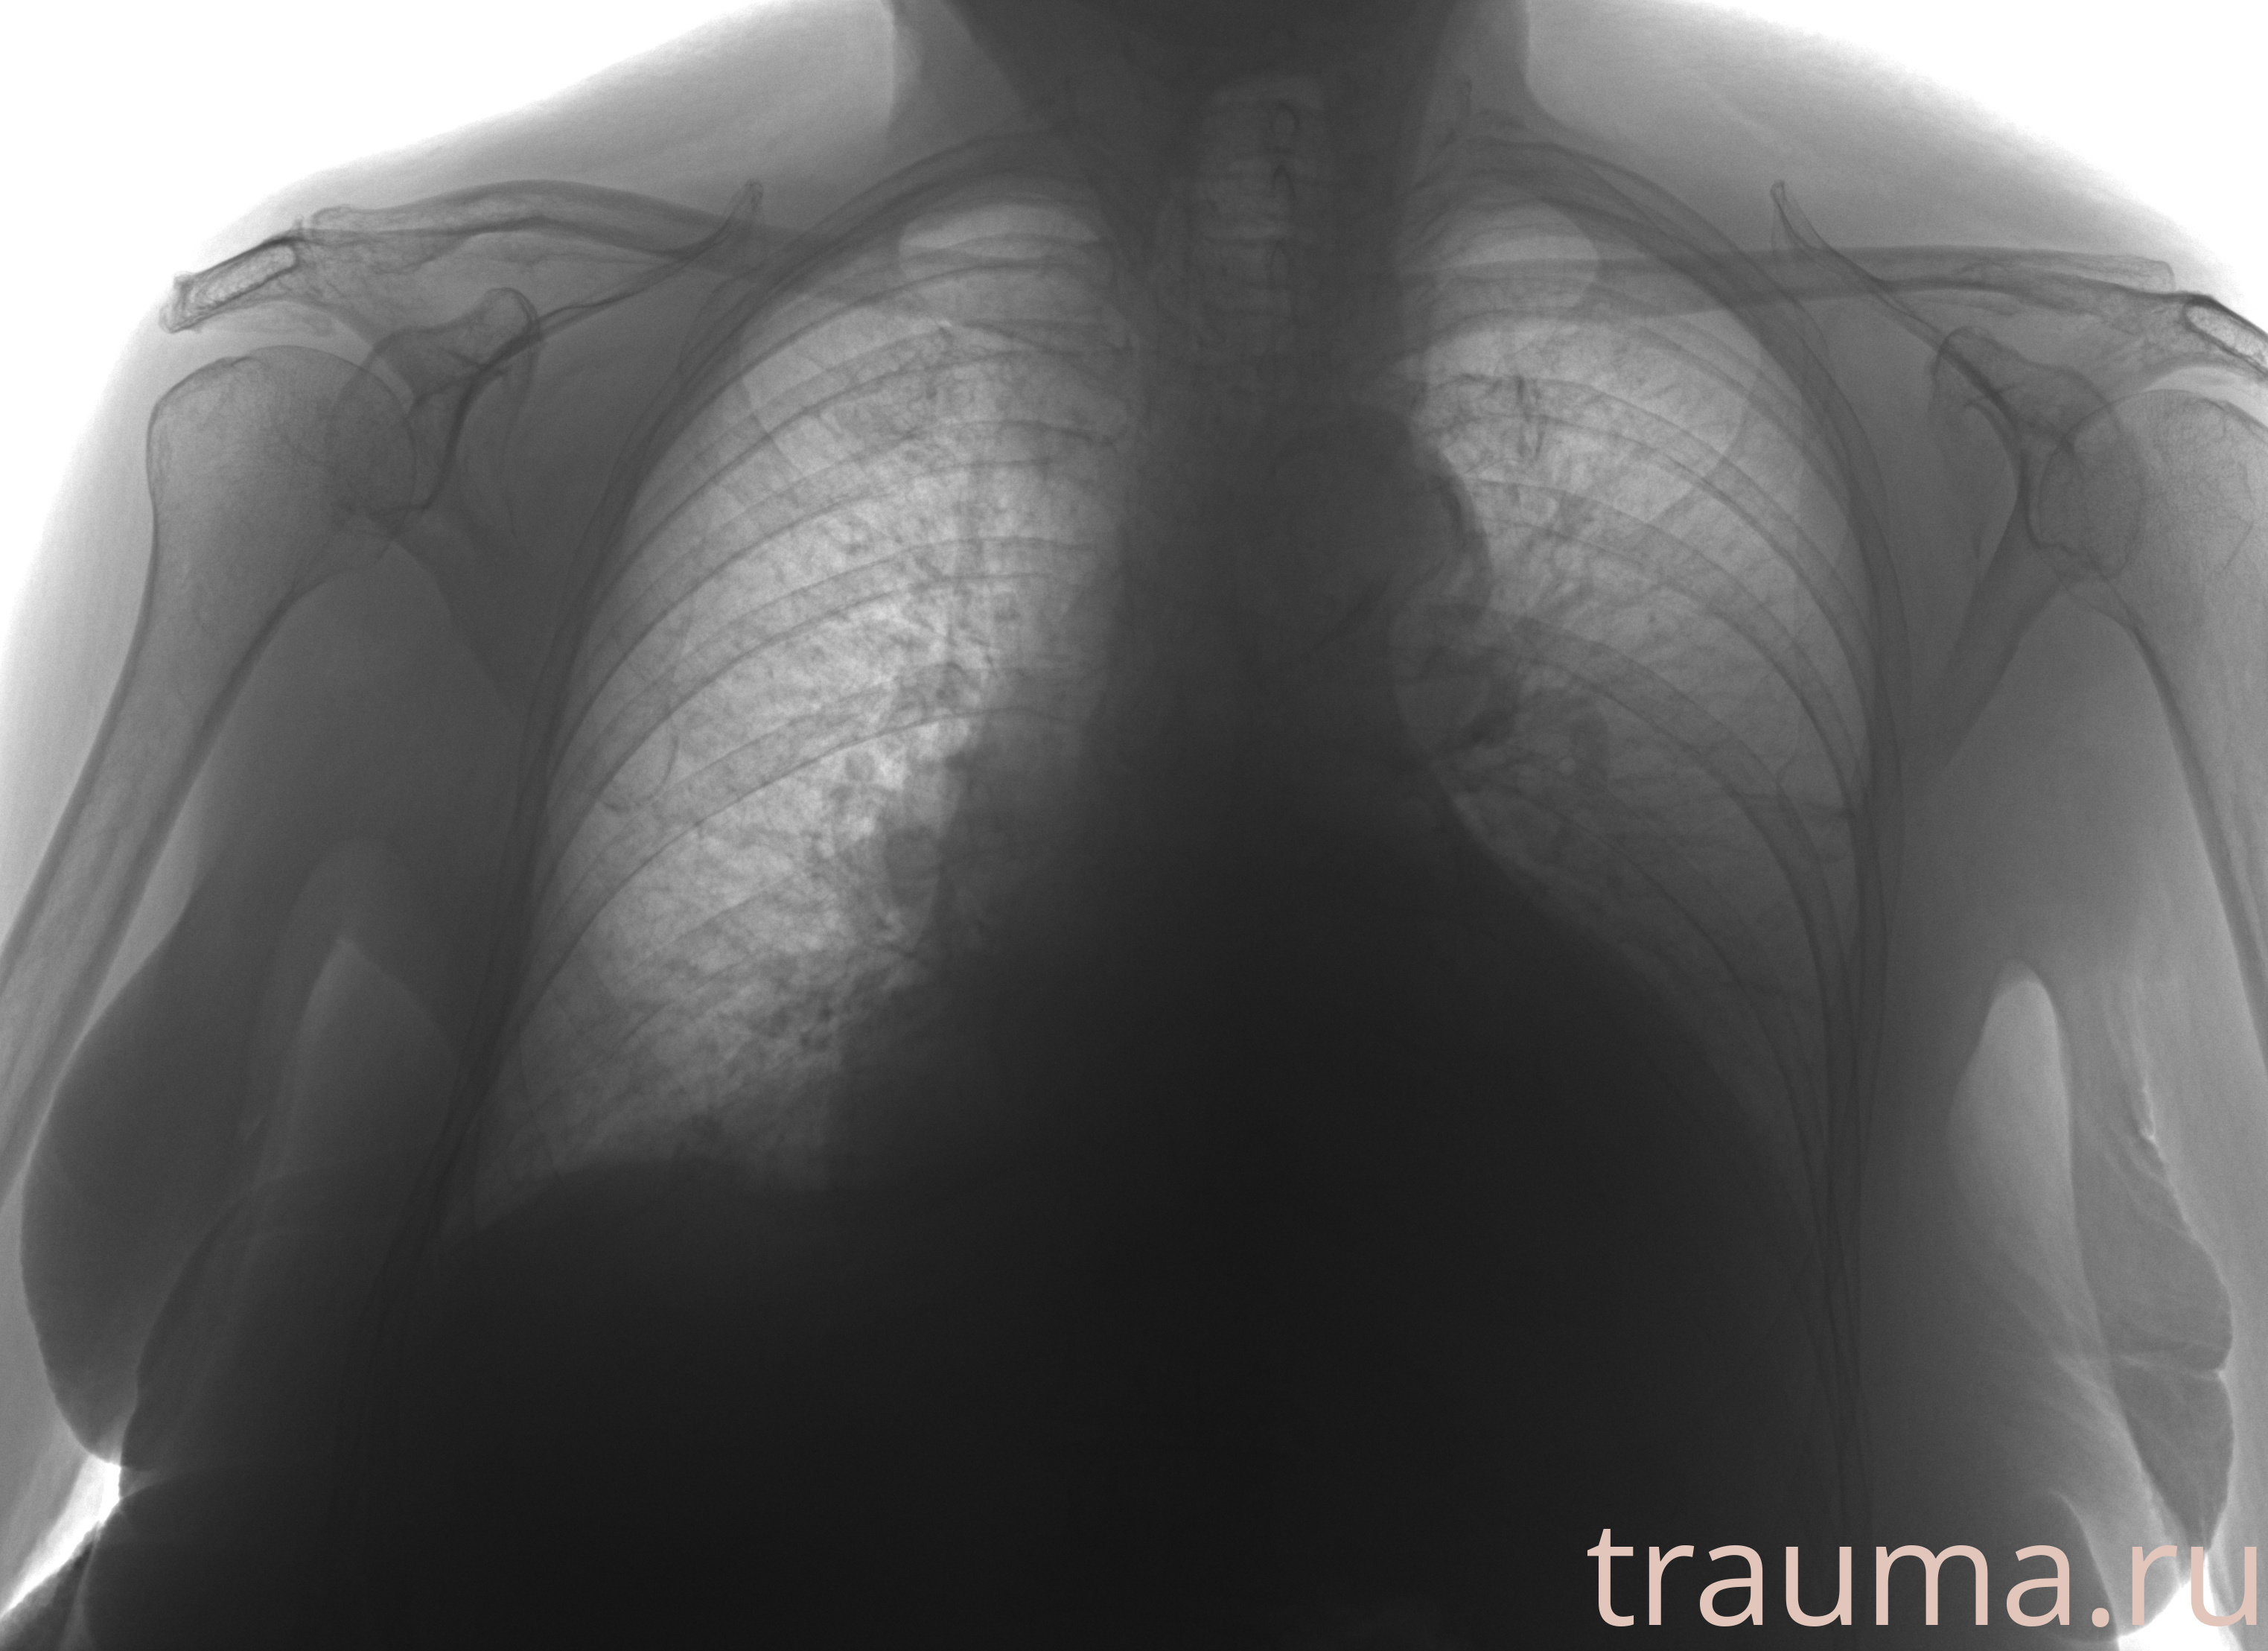

Рентген на дому: по вашему адресу приезжает врач-рентгенолог, травматолог-ортопед с мобильным рентгеновским аппаратом, проводит диагностику травмы или заболевания, делает необходимые рентгенограммы, дает рекомендации по дальнейшему лечению. Получить качественные снимки в домашних условиях возможно благодаря уникальной методике, разработанной МосРентген Центром для института  Склифосовского

при переломе шейки бедра и пневмонии от компании МосРентген Центр - партнера Института имени Склифосовского